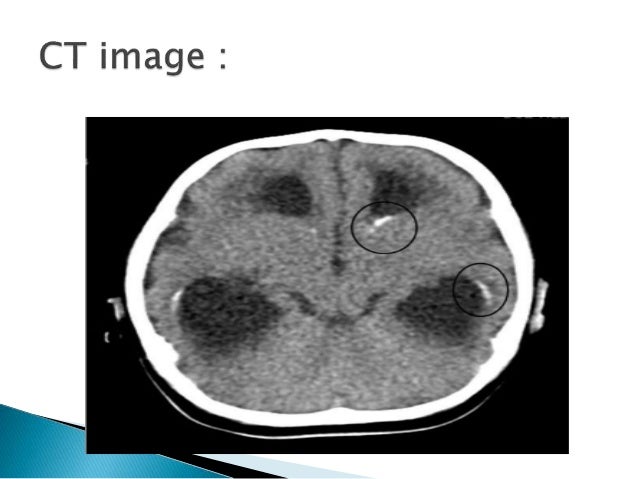

11. 11.  A known AIDS patient presents with complaints of fever, seizures, visual defects and facial nerve palsy and altered sensorium.  His CD4 count is 78/ul  CT scan brain shows multiple ring enhancing lesions in the basal ganglia

12. 12.  A newborn baby is presenting with visual impairment, microcephaly, hydrocephaly and on CT scan it showed intracerebral calcification.